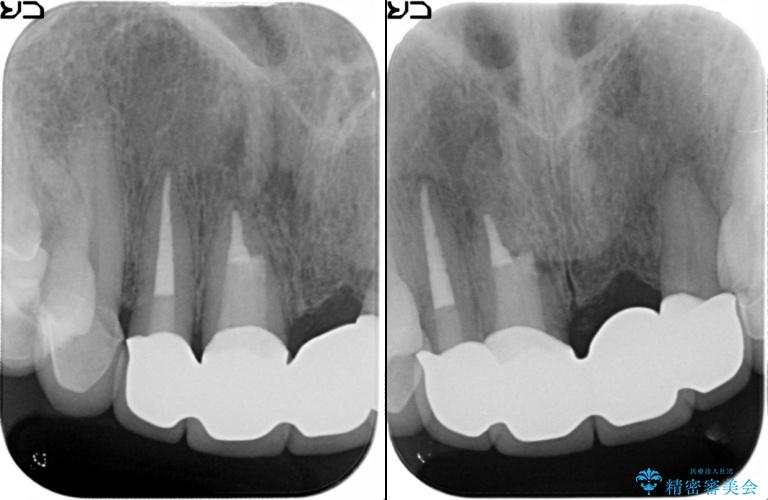

[ セラミック治療 ] 歯ぐきの際の黒ずみを改善したい

- 歯ぐきとセラミックの間の黒ずみが目立つので、きれいに治してほしい。と希望され来院されました。

歯ぐきの位置が変化しクラウン下の歯が見えるようになってしまったことで、審美障害が生じている状態です。

クラウンマージンの再設定を行うことで、黒ずんだ部分を再度覆い、審美障害を改善します。

歯ぐきの位置の経年的な変化は、誰にでも起きうる変化です。

強いブラッシングや電動歯ブラシの当て過ぎなども原因の一因となることがあります。